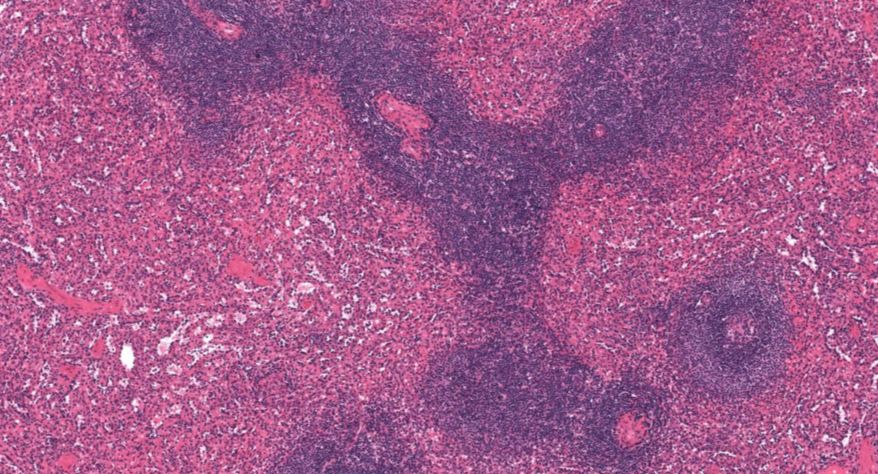

低倍镜:胸腺表面包有薄层结缔组织构成的被膜,结缔组织深入实质,将胸腺分成许多不完整的小叶。每个小叶分为周围的皮质和中央的髓质两部分。皮质中胸腺细胞排列密集,故染色深;髓质中胸腺细胞较少,胸腺上皮细胞多,故染色浅,其中可见染成红色的圆形小体-胸腺小体。高倍镜:胸腺小体大小不等,由几层至十几层扁平的胸腺上皮细胞呈同心圆状排列而成,其外周的细胞较幼稚,细胞核明显;小体中央部分的上皮细胞已退化,细胞核消失,胞质呈均质状,染成红色。

3.皮质

4.髓质

5.胸腺细胞

6.胸腺上皮细胞